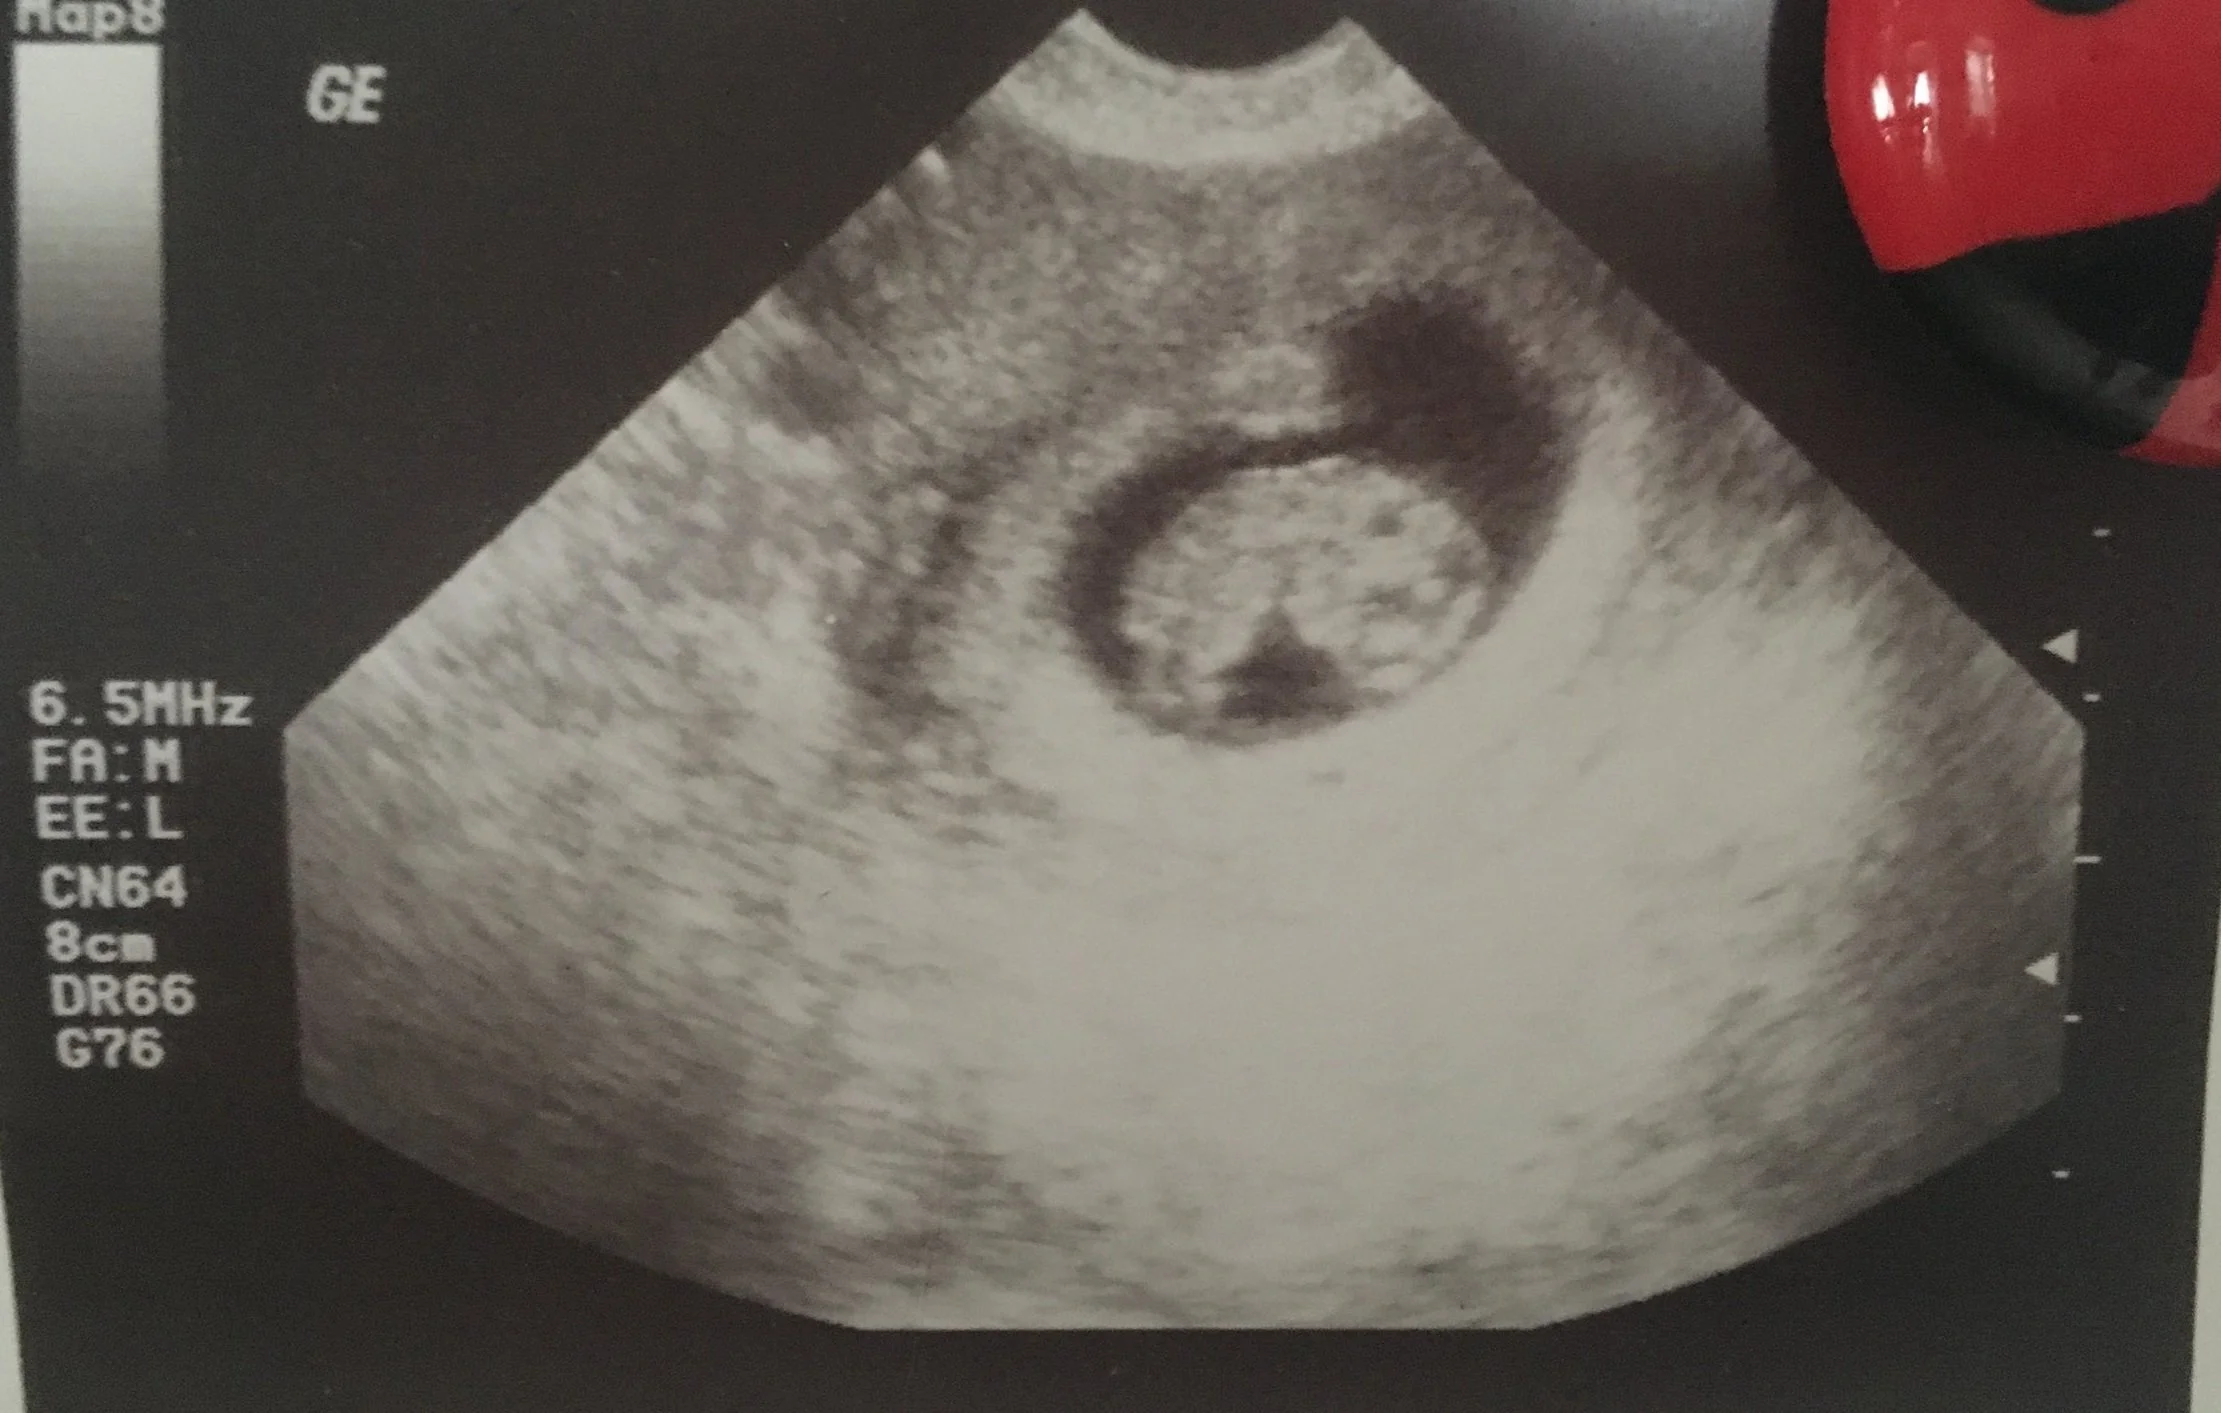

6.5 weeks pregnant and we finally saw a healthy beating heart.